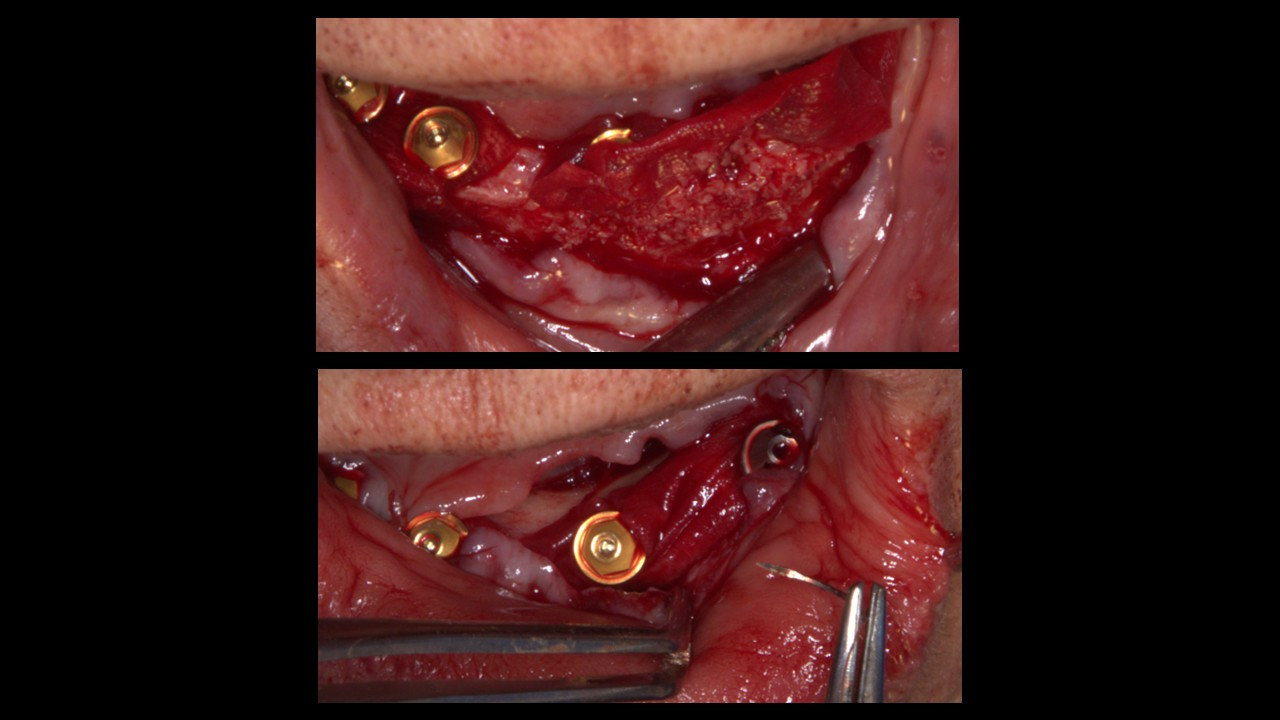

Técnica:

• Exodoncia dientes 4.3, 3.3 y 3.4.

• Colgajo espesor total en grupo V.

• Instalación de guía CX para desgaste de reborde óseo.

• Instalación de guía CX para posicionamiento de IOI (posiciones 4.5, 4.3, 4.1, 3.3, 3.5).

• Regeneración ósea guiada en relación a reborde óseo y alveolos de exodoncias. Cierre con membrana colágeno.

• Prueba de estabilidad primaria en IOI que serán cargados.

• Instalación de pilares multiunit en IOI que serán cargados. Prueba de coincidencia con pilares temporales en provisorio.

Materiales:

• Implantes dentales Osstem TSIII Superficie SOI Ø4.0x8.5mm (#1), Ø4.0x10mm (#5), Ø3.5x10mm (#2, #3, #4).

• Aloinjerto "Allo Oss", 1cc.

• Membrana de colágeno "OssGuide", 20*30mm (2).